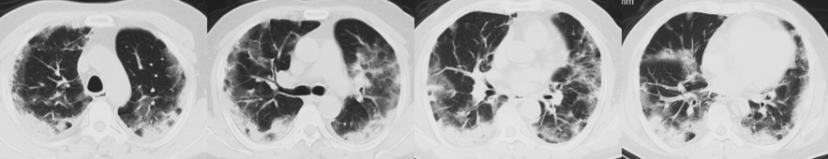

1月9日4:00患者血压下降[60/40 mmHg,去甲肾上腺素1.4 μg/(kg·min)],心率120~130次/min,PFR由200 mmHg降至106 mmHg。调整治疗策略:更换PICC、动脉/拔除血滤管,多黏菌素+替加环素+阿米卡星+万古霉素抗感染,补液:2023年1月9日和10日共补液11000 ml,去甲肾上腺素剂量由1.4下调至1.0 μg/(kg·min)。1月10日胸部CT示:肺内渗出增多,符合COVID-19特点。

图片

患者2023年1月10日胸部CT

2023年1月10日BALF NGS阴性,WBC/PCT无继续升高,新冠核酸CT值35,IL-6 3090 pg/ml。予甲强龙(80 mg qd)联合托珠单抗治疗,去甲肾上腺素逐渐减量,至1月13日停用,1月16日患者影像学明显改善。

患者2023年1月16日胸部CT

这例患者在最初病情好转后,我们将抗炎药物减量,但后期出现了较严重的炎症“反弹”。